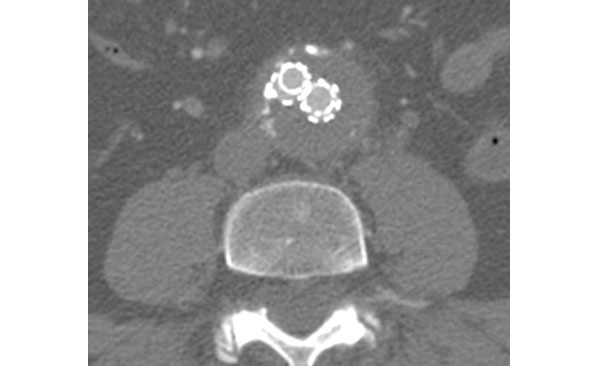

Άνδρας ασθενής 64 ετών με ανεύρυσμα κοιλιακής αορτής μέγιστης διαμέτρου 6,5 εκατοστών, χωρίς συμμετοχή των λαγονίων αρτηριών και με παρουσία βατών οσφυϊκών αρτηριών καθώς και κάτω μεσεντερίου αρτηρίας

Ενδαγγειακή αντιμετώπιση με την τεχνική της πλήρωσης του ανευρυσματικού σάκου με πολυμερές με χρήση των μοσχευμάτων Nellix, με σκοπό την αποφυγή ενδοδιαφυγής τύπου ΙΙ

Διαδερμική τοποθέτηση των μοσχευμάτων με βάση την καλή ποιότητα των μηριαίων αρτηριών, την κατάλληλη σωματοδομή του ασθενούς και την ιδιαίτερα χαμηλή διάμετρο της συσκευής εισαγωγής του μοσχεύματος